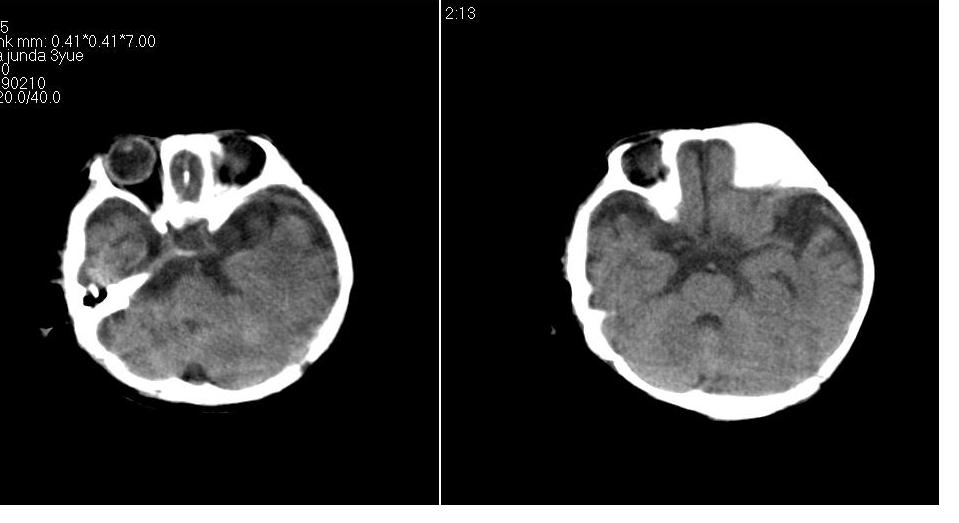

标题: PED1744:颅脑CT平扫

男 3个月,头大,颈软,头向后仰。

外部性脑积水

考虑外部性脑积水。

脑外间隙增宽,未见明显异常。

脑外间隙增宽,余未见明显异常。

脑外间隙增宽,现在好像有人说是一种发育性的交通性脑积水

蛛网膜增宽,外部性脑积水?

外部性脑积水(也就是诸位说的脑外间隙增宽);脑实质内未见异常密度灶,脑室系统无扩张,建议随访,毕竟临床症状听着怪吓人的。